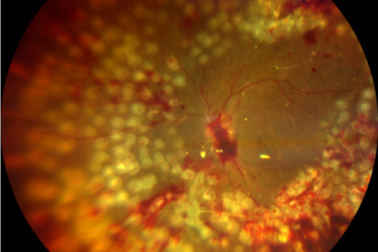

糖尿病盯上「眼底」,警惕这些致盲隐患!

2026-04-24 -